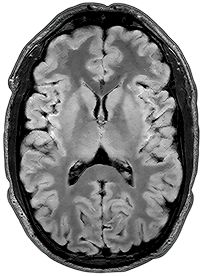

3D FLAIR

1.5T

1 x 1 x 3mm

3:31

0.5T

3:15